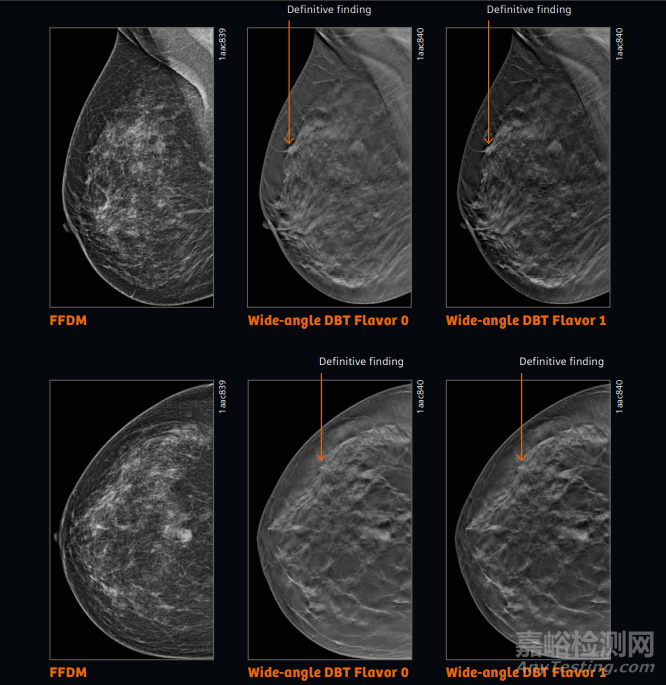

方便快捷:采用廣角層析成像技術(shù),可在短時(shí)間內(nèi)實(shí)現(xiàn)業(yè)界最大50度廣角3D攝影。

這是目前市場(chǎng)上產(chǎn)品能提供的最大角度。加上大約5秒的掃描時(shí)間,僅為過(guò)去所需時(shí)間的1/5,提高病變檢出率。

圖像質(zhì)量高:采用全新開發(fā)的 Flying Focus Spot 管和 Premia AI 重建技術(shù),提高圖像質(zhì)量。

這是 Flying Focus Spot 技術(shù)首次應(yīng)用于乳腺X線攝影,可以防止X 射線管高速移動(dòng)而造成的圖像模糊效果。即使在非常高的掃描速度下,也能產(chǎn)生清晰的3D圖像。

在層析成像中,X 射線管圍繞乳腺繞圈移動(dòng),而傳統(tǒng)檢查中 X 射線管保持靜止來(lái)創(chuàng)建三維圖像的。

與目前的乳腺攝像儀器相比,MammoMat B.brilliant 通過(guò)進(jìn)行同源性攝影,可以去除乳腺組織的重疊,清楚地描繪出病變。

因此可以減少假陽(yáng)性病例的發(fā)生,提高早期乳腺癌的篩查能力,減少醫(yī)療費(fèi)用。